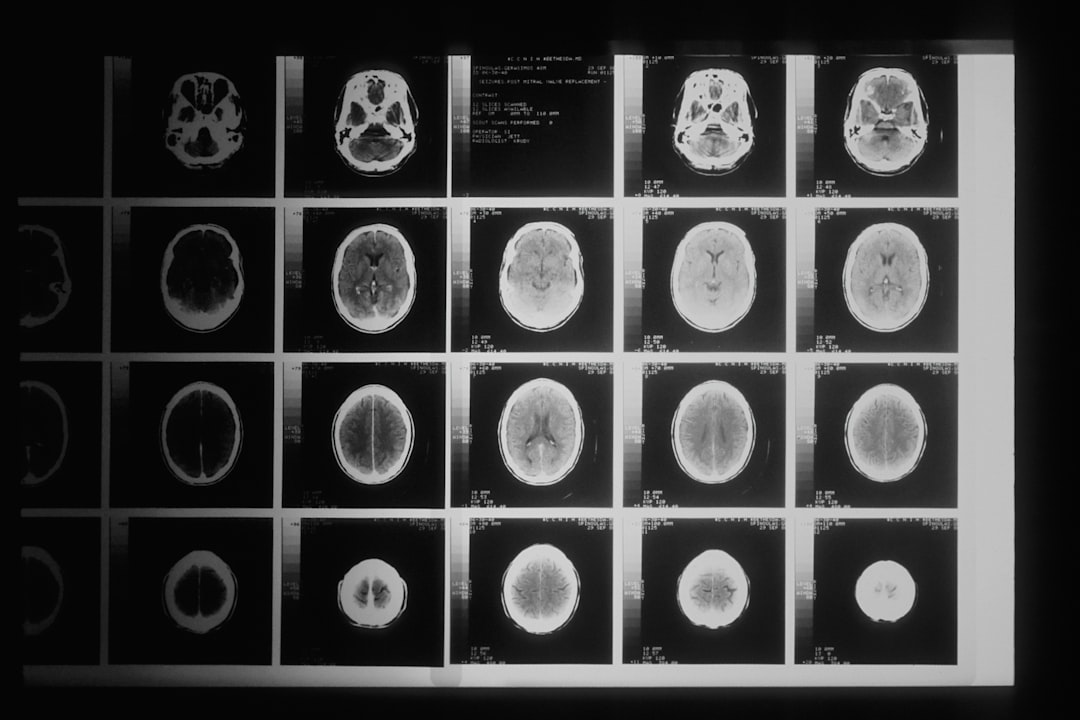

I tillegg kan bildediagnostikk som MR eller CT-skanning være nødvendig for å identifisere eventuelle svulster eller abnormiteter i hypofysen eller binyrene. Disse bildene gir legen din verdifull informasjon om strukturen til disse organene og kan hjelpe med å bekrefte diagnosen. Det er viktig å være tålmodig gjennom denne prosessen, da det kan ta tid å få en nøyaktig diagnose og utvikle en passende behandlingsplan.